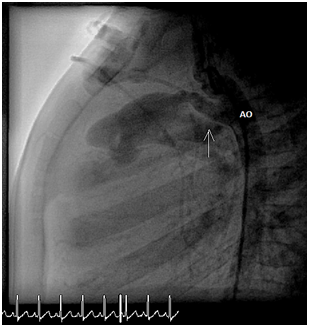

The PDA was not crossed with wire or catheter and the PDA narrowest diameter was 1mm. Flipper Cook coil 3mm by 4 was delivered through 4F multipurpose catheter and deployed in the ductus arteriosus successfully. Follow up angiography demonstrated there was a residual flow around the coil. After short time, the coil embolized to right pulmonary artery. Snare was introduced and the coil was snared out successfully without complications. Then 6.5mm by 4Flipper Cook coil was delivered. After deployment, an angio test confirmed that the coil was in a good position. There was minimal residual leak around the coil. Several minutes later, the coil was embolized to the left pulmonary artery, again snare was re-introduced. There was difficulty toretrieve the coil at the level of tricuspid valve.  Then it was brought down till groin, but could not be snared out. Cardiac surgeon did cut down and coil removed without major complications repeated aortic angiogram was done showed large tubular PDA about 4mm (Figure 10).

Left femoral vein was cannulated and 7Fdelivery sheath introduced. PDA amplatzer duct occluder 6mmx 8mm delivered and closed the PDA successfully. Follow up angiogram showed minor leak through the device (Figure 11).

Figure 10 Angiogram: Large PDA.

Figure 11 Angiogram: Device in place.